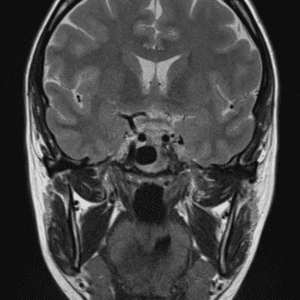

Case #28

Medulloblastoma